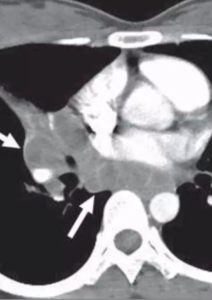

10-year-old child with tuberculosis, shows widening of the right paratracheal stripe

CECT show tuberculous nodes that show central areas of low attenuation suggestive of caseous necrosis and peripheral rim enhancement.

TUBERCULOUS NODE